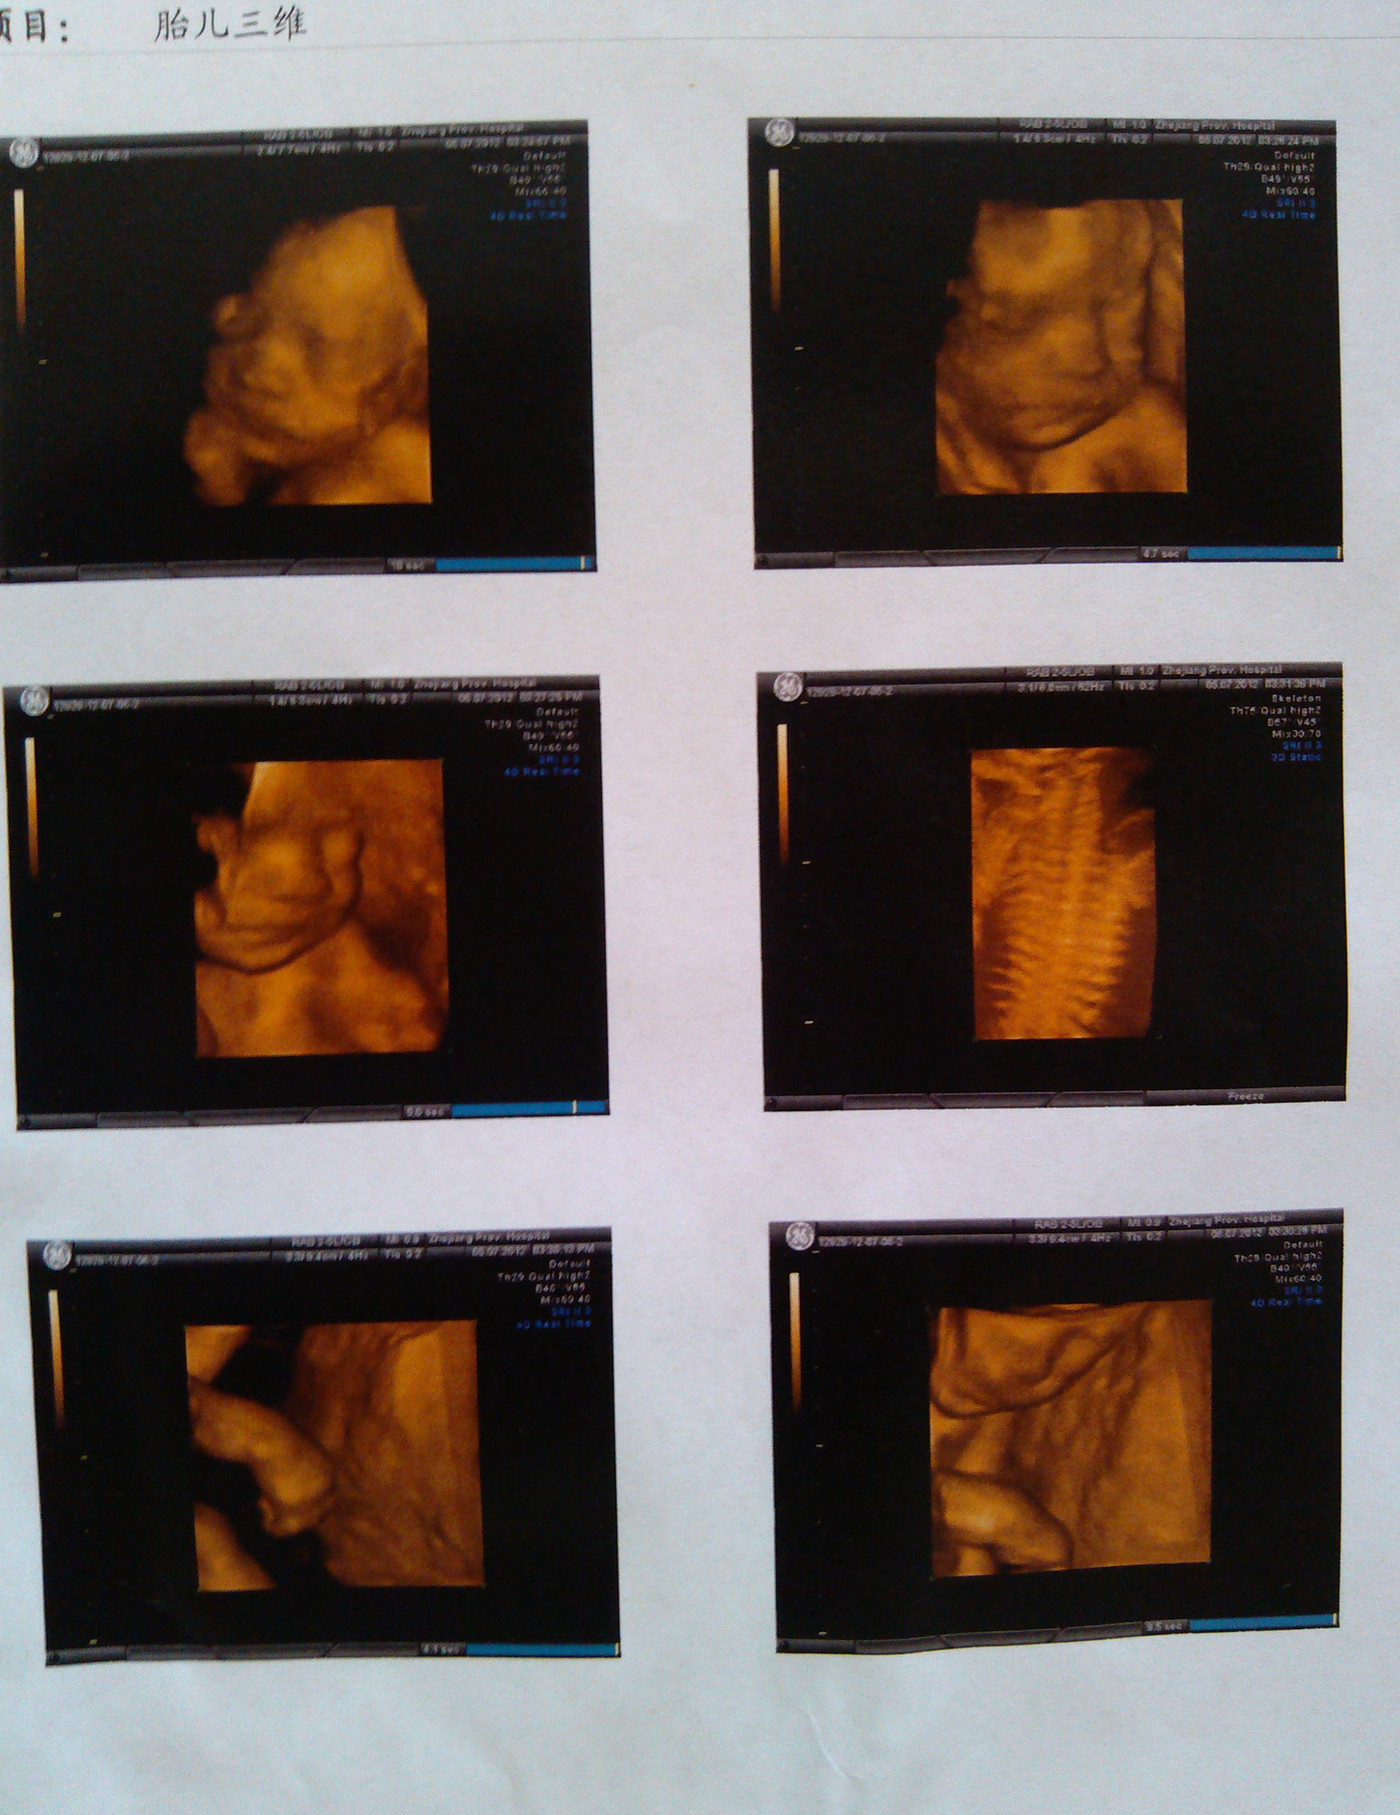

24周+3天在邵逸夫做的三维b超

1920x1080 - 318KB - JPEG